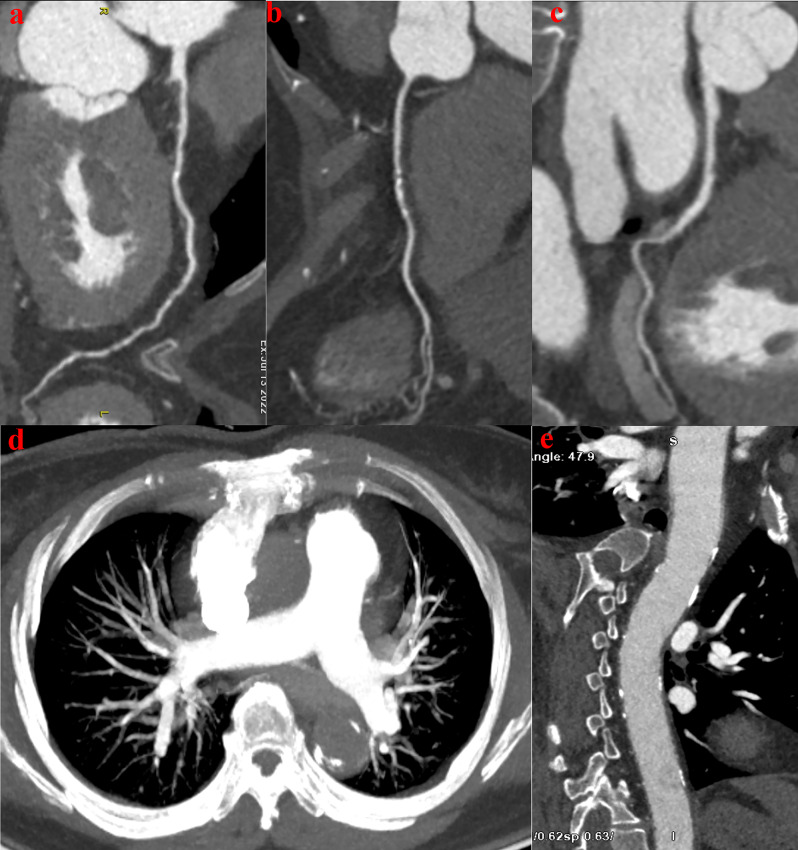

Background: The triple rule-out computed tomography angiography (TRO-CTA) has recently emerged as a technique that noninvasively evaluates the coronary arteries (CAs), the pulmonary arteries (PAs) and the thoracic aorta (TA).

Objective: To evaluate the feasibility of an optimized scanning protocol to reduce the volume of iodine contrast media (ICM), injection rate, and radiation dose in patients undergoing TRO-CTA.

Methods: Patients undergoing TRO-CTA were assigned to either group A or group B using a 16 cm wide-detector CT. Patients in group A were imaged with a traditional triple scanning protocol with a sequence of the PA, CAs, and TA. Patients in group B were imaged using the modified protocol with scanning sequence of PA, TA, and CAs, ICM of 55 ml, and injection rate of 4.5 mL/s. The image quality and effective radiation dose (ED) were compared.

Results: There were no significant differences in basic information between groups A and B. Other than the left PA, RA, and RV, there were no significant differences in the CT attenuation values of relevant vascular structures between groups A and B. There were no significant differences in CNR values between the two groups except the LAD-D and LCX. The image quality scores were comparable between groups A and B except the CAs. However, there were significant differences between the two groups in ICM (p < 0.05), scanning time (p < 0.001) and ED (p = 0. 023).

Conclusions: The optimized TRO-CTA scanning protocol can achieve less ICM and lower ED while maintaining image quality.